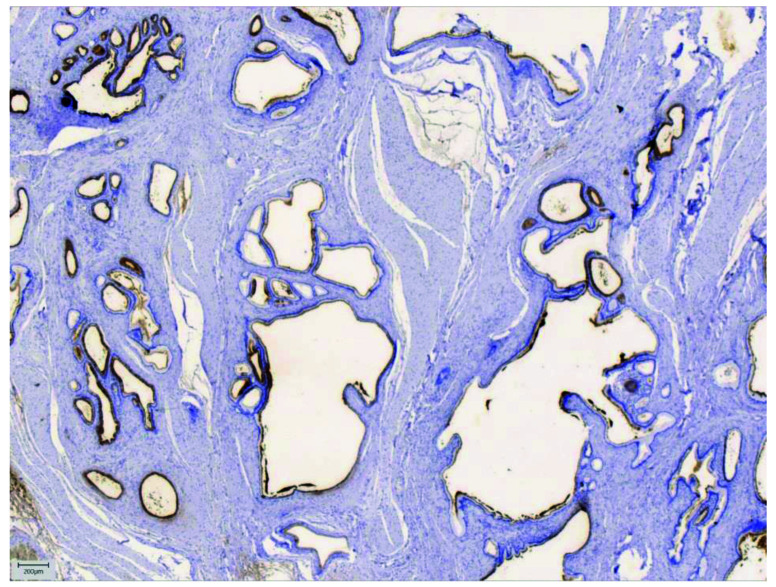

Pancreatic heterotopia is a relatively rare condition that implies pancreatic tissue anatomically separated from the main gland, showing no vascular or ductal continuity. It is known to occur in many sites of gastrointestinal tract, with stomach being the most common one. This case is of great interest because ectopic pancreatic tissue in jejunal wall presented as bowel obstruction. The aim of this article is to provide a review of clinical, histopathologic and immunohistochemical features of ectopic pancreatic tissue in jejunum, emphasizing the possible diagnostic pitfalls in gastrointestinal tract, especially in its upper parts. Knowing the most common locations, imaging features and histopathologic criteria, the diagnosis of pancreatic heterotopia could be successfully set preoperatively. Associated complications are various and sometimes difficult to handle, so accurate and precise diagnosis, as well as surgical resection, is often needed.

Abstract Image